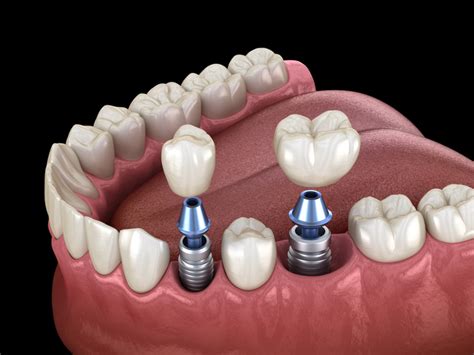

La implantología es una rama de la odontología que se enfoca en la colocación de implantes dentales para reemplazar dientes perdidos. Para las personas sin dientes, también conocidas como pacientes edéntulos, la implantología ofrece una solución duradera y funcional. Los implantes dentales consisten en raíces artificiales que se insertan en el hueso maxilar o mandibular, proporcionando una base sólida para prótesis dentales fijas, como coronas o puentes, mejorando significativamente la función masticatoria y la estética facial.

- Implantes convencionales: Los implantes convencionales son ideales para pacientes con suficiente densidad ósea en la mandíbula o el maxilar. En casos de edentulismo total, se pueden colocar múltiples implantes que sirvan de soporte para prótesis completas. Este enfoque suele ser más adecuado para pacientes con buena salud ósea y sin necesidad de reconstrucciones óseas significativas.

- Implantes All-on-4: Este sistema utiliza cuatro implantes estratégicamente colocados en cada arco dental (superior o inferior) para soportar una prótesis fija completa. Es una opción muy popular para personas sin dientes, ya que permite rehabilitar todo el arco dental con una menor cantidad de implantes, reduciendo el tiempo de tratamiento y el coste.

- Procedimiento de colocación de los implantes: Durante la cirugía, los implantes se insertan en el hueso maxilar o mandibular bajo anestesia local o sedación. Dependiendo del tipo de implante y la condición del paciente, la colocación de una prótesis provisional puede realizarse el mismo día o después de un periodo de osteointegración, que suele durar entre 3 a 6 meses.